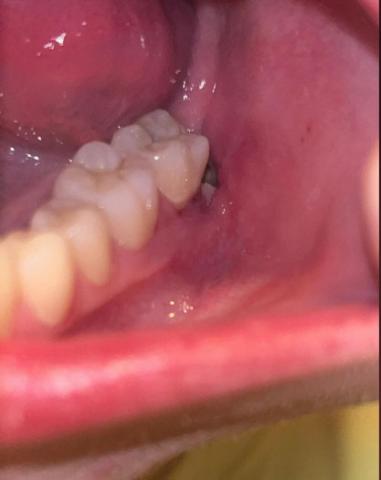

The image shows a posterior lower molar area with an open extraction socket behind the last visible tooth. Surrounding gum tissue appears reddish and inflamed, with possible food debris or clot disruption. This presentation is commonly associated with delayed healing or early dry socket risk.

Clinical Findings (Zoom 100% Analysis)

Tooth & Socket Area

Missing posterior molar (recent extraction site)

Socket appears partially open

Possible loss or thinning of blood clot

Mild grayish area inside socket (possible debris or exposed bone)

Gum & Soft Tissue

Redness around socket margins

Mild swelling of surrounding gingiva

No visible pus, but inflammation is present

Adjacent Teeth

Neighboring molar appears intact

No obvious caries on adjacent tooth

Gingival margin near adjacent tooth slightly irritated

Primary Diagnosis

Delayed post-extraction healing with risk of dry socket (alveolar osteitis)